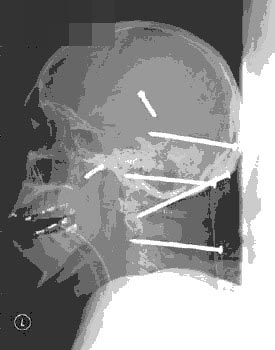

马克内认为,大部分人只利用了大脑的3%——10%,而他则利用了大脑能量的25%。他是唯一一个做到这一点并被医学界注意的人。科学家通过CT和MRI扫描发现这位64岁老人的松果体只相当于20岁的年轻人。

8——9个月以后饥饿的感觉逐渐下降,直至彻底消失。 马克内认为,大部分人只利用了大脑的3%——10%,而他则利用了大脑能量的25%。他是唯一一个做到这一点并被医学界注意的人。科学家通过CT和MRI扫描发现这位64岁老人的松果体只相当于20岁的年轻人。